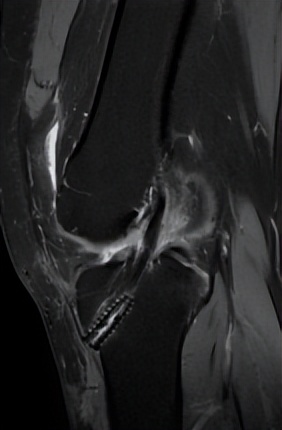

△术后CT复查可见悬吊钢板和挤压钉位置良好(左图),MRI显示重建的前交叉韧带(右图)

手术中,何河北医生采用微小切*技口**术,取出小张膝盖同侧的半腱肌,将肌腱编制后,再在关节镜下,于股骨以及胫骨建立骨隧道,使用可调节袢将肌腱悬吊在股骨隧道侧,最后用可吸收挤压钉将胫骨侧固定。

手术半年后,小张的膝关节活动自如,她终于可以重返球场。